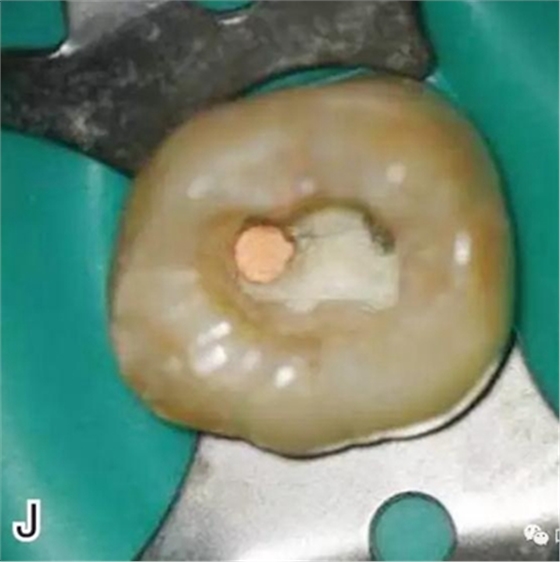

8、熱牙膠根中上段的充填

在完成根尖段的充填后,使用熱塑牙膠注射儀對根管中上段進(jìn)行分層充填,一般分2~3次完成充填,每次充填均使用相應(yīng)直徑大小的垂直加壓器進(jìn)行加壓。拍片確認(rèn)充填效果(圖8)。

圖8 熱牙膠根中上段的充填,A、B.注射儀注射中段熱牙膠

C、D.垂直加壓器加壓 E、F.注射儀繼續(xù)注射上段熱牙膠

G、H.垂直加壓器加壓 I、J.完成根中上段的充填